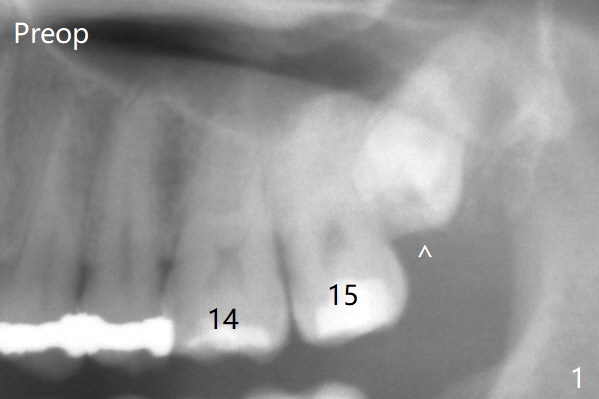

A 37-year-old man complains of food impaction between #14 and 15. Panoramic X-ray shows mesioangular impaction of #16 (Fig.1 ^), which may press #15 root to rotate the tooth so that there is a diastema between #14 and 15. When the impacted tooth is removed, it looks like a microdontia. Intraop X-ray reveals a normal sized 3rd molar in situ (Fig.2: 16). Therefore the microdontia removed is a supernumerary tooth. The tooth #16 is then extracted. The diastema appears to persist 2 years 7 months postop (Fig.3), although gingival swelling and pain reduces. The follow up panoramic X-ray reveals a significant increase in PARL at #20. Return to Professionals Xin Wei, DDS, PhD, MS 1st edition 05/14/2020, last revision 05/16/2020